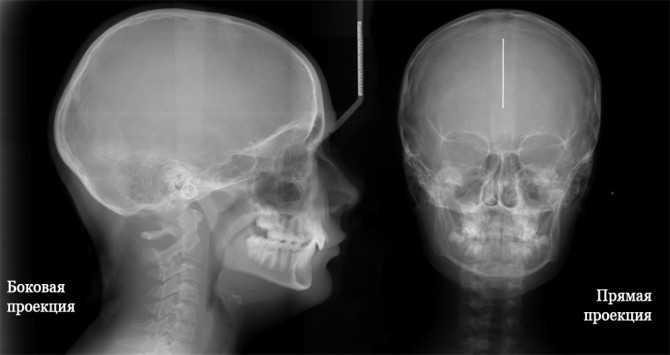

Краніографія

Аналіз стану кісток черепа проводиться у випадках його пошкодження за допомогою рентгенографії. Дослідження не викликає ніяких відчуттів. Доза отриманого опромінення при рентгенографії черепа незначна і підбирається індивідуально. Робляться знімки обстежуваного черепа в бічній і фронтальній проекції.